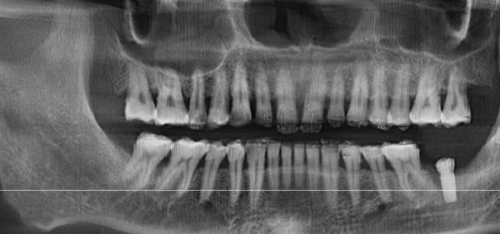

济南众牙口腔医院的核心医生团队均具备10年以上临床经验,多位医生拥有国有医院工作背景,技术实力值得信赖。总技术院长姜宝岐是山东大学口腔医学本硕,原山东省口腔医院种植中 心主事,从业28年,任山东口腔医学会副会长,主编《口腔种植技术》专著,擅长穿颧种植、全口即刻负重,手术精度达微米级。正畸科主事朱鹏飞是3D数码隐形矫正认证医师,完成超千例矫正病例,结合面部美学设计方案,尤其擅长骨性龅牙掩饰性矫正。种植医生王希太是副主医师,专注种植15年,多次赴德研修,擅长微创种植、ALL - ON - 4半口修复,患者评价“术中舒适,当天吃苹果”。而且,医院医生定期参加国内外学术交流,掌握新技术,如即刻种植、数字化正畸等新技术应用成熟。